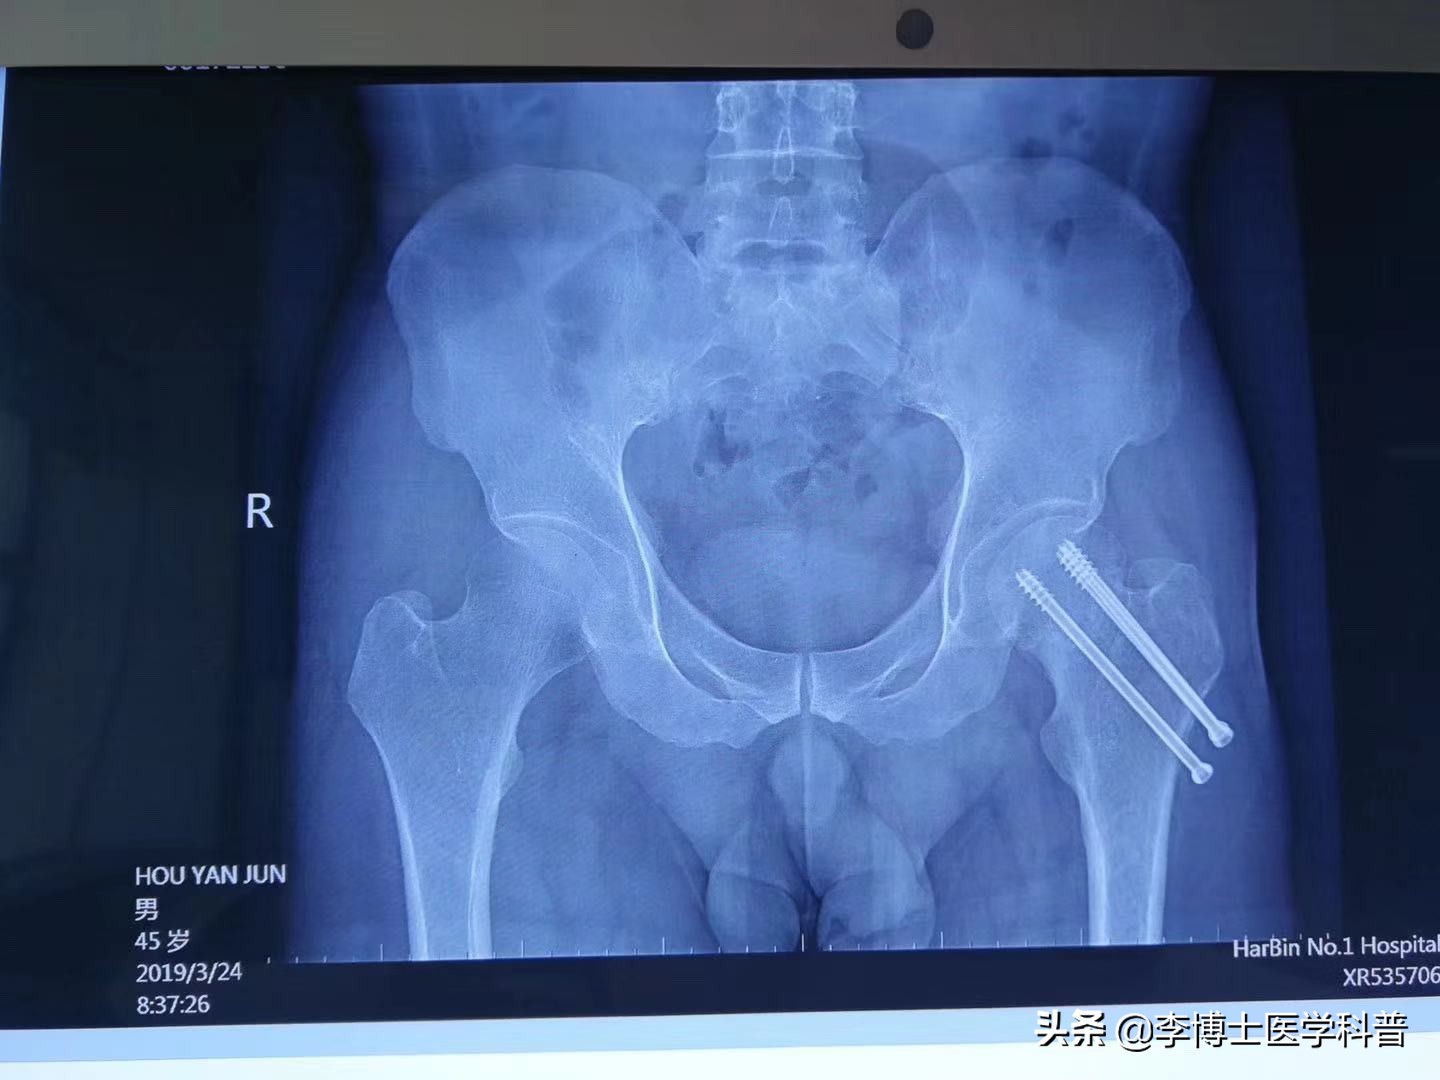

今天科室来了一个患者,患者三年前由于车祸股骨颈骨折,当时在外院行股骨颈内固定治疗,治疗后近三年,骨折线明显,有内固定松动迹象。

患者辗转多家医院,告知等待股骨头坏死后行人工关节置换,但是患者年轻,不想行人工关节置换,慕名找到李博士,李博士给予精准定位后聚焦式冲击波联合PRP技术,治疗3个月后,效果明显,在不用置换的前提下,骨头长上了,不用手术了。